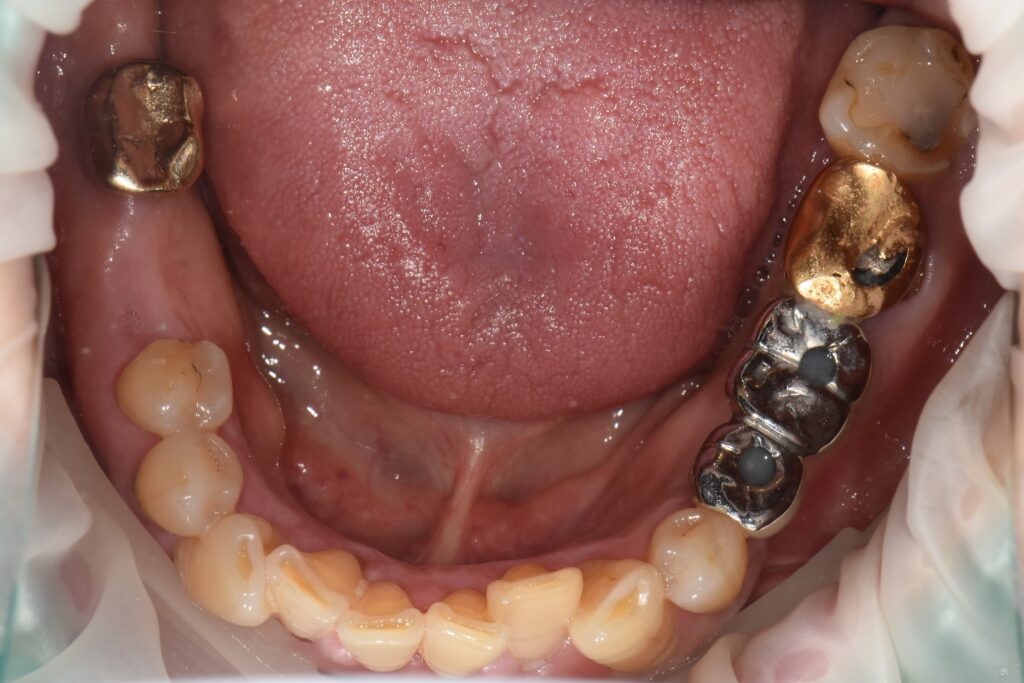

하치조신경 전달마취 하에 #37 난발치를 시행하였습니다.

치아는 골 유착으로 인해 단순 발치가 어려워 BURR를 이용한 치근 분할 후 발치를 진행하였으며,

발치 후 봉합(suture)까지 시행하였습니다.